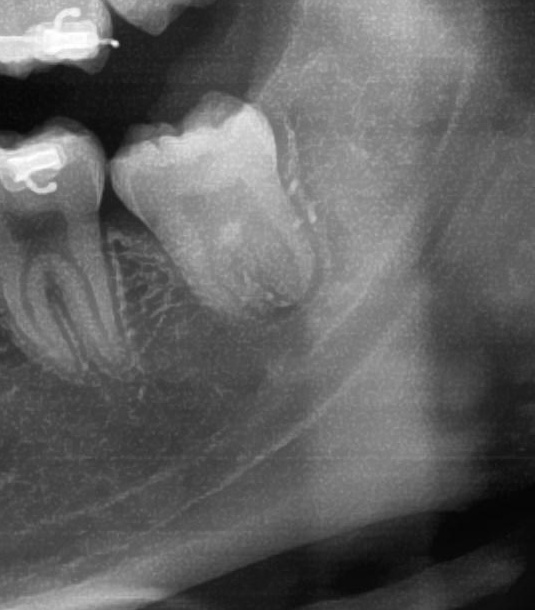

次にパノラマ写真を撮影してみると、左下の親知らずは手前の歯と並んでをまっすぐに生えているのが確認できました。

さらに、下顎の親知らずは下歯槽神経に非常に近いところに生えている場合もあるため、CTで詳しい解析を行います。

親知らずが生えている位置が、神経に近い、あるいは神経に当たっている場合は、大きな病院に紹介する場合もあります。

親知らずの根っこは下歯槽神経から十分に距離があることが分かりました。